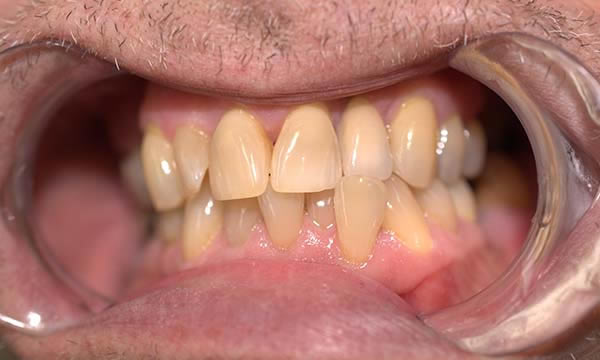

Case H

This case is a collaboration between ourselves and a specialist periodontist based in the referring practice. A case of patience, where a patient wanted to be rid of his un-retentive denture replacing the UL1 while stabilising his periodontal disease with improved home care and treatment from a specialist periodontist.

After approximately 12 months of periodontal therapy, the patient was deemed stable enough by the specialist periodontist to undergo implant treatment. An Astra EV implant was placed and a well shade matched zirconia crown was luted to an Atlantis abutment. Digital SLR pictures were used to provide the lab technician with appearance detail of the neighbouring dentition, to allow the technicians at Smile Dental Laboratory to introduce 'accents' and a realistic and seamless look to the final zirconia prosthesis.

During Treatment